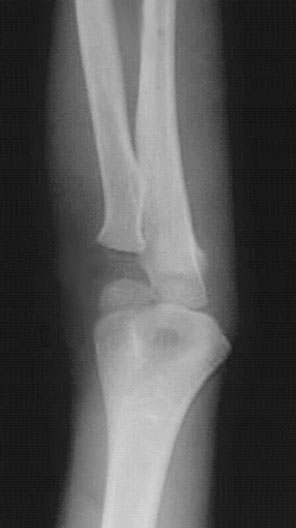

Elbow Dislocation

*Arrows point to dislocation